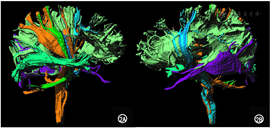

磁共振张量成像:左侧基底节区、额颞叶软化灶伴左侧皮质脊髓束、左侧皮质核束损害伴重塑改变;左侧胼胝体纤维减少;双侧视辐射尚对称,如图2所示。